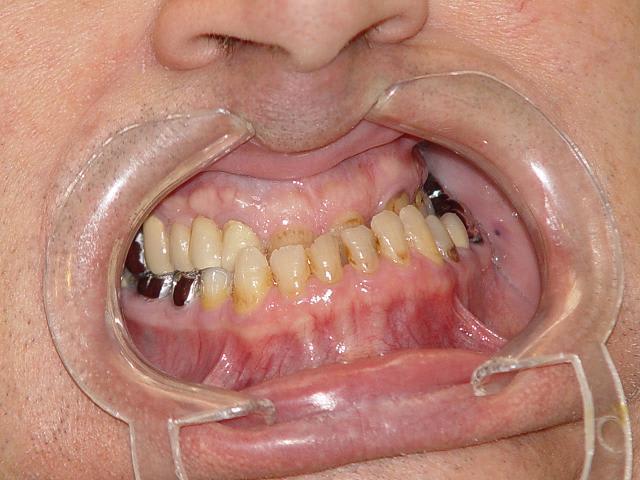

Le patient m'a donné lui même la DVO a obtenir avec une cire de déglutition, trop long à expliquer, cf dentosophie.

je me suis efforcée à rétablir une position d'équilibre en alignant tant faire se peut les milieux incisifs et en remontant le plus possible la DVO complètement effondrée.

Le cas a débuté le mois dernier et voici la suite en sachant que tout ce qui est fait actuellement est en temporaire.

Classe iii avant traitement uasubx - Eugenol

Classe iii avant traitement vue endo bucale myikgy - Eugenol

Suite du cas dentosophie classe iii whkbzy - Eugenol

Suite du cas dentosophie classe iii tout en temporaires axign4 - Eugenol